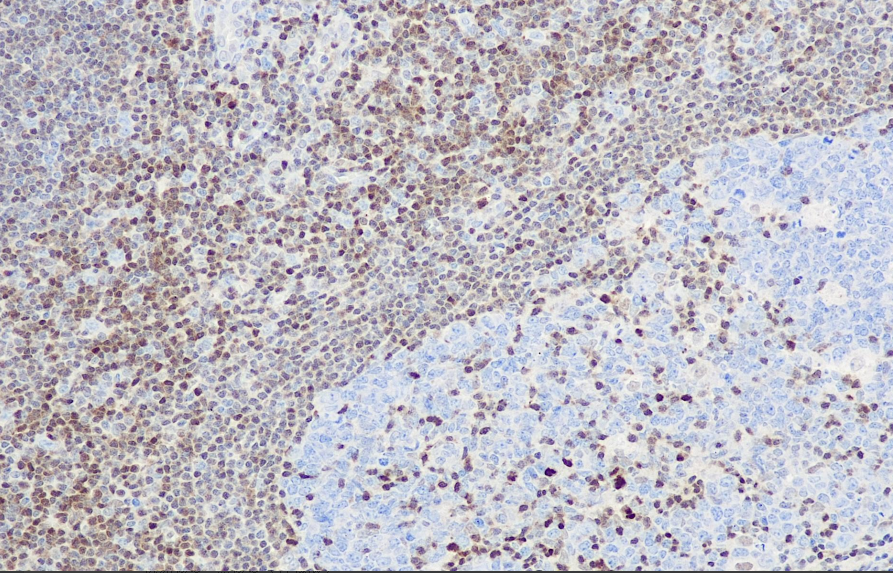

Cellular localization: nucleus

Positive control: tonsils

p27 is an inhibitory factor that regulates cell cycle mitosis. It regulates the process of the cell cycle from the G1 phase to the S phase by binding to or inhibiting cyclins or cyclin-dependent kinases. Low expression of p27 is generally accompanied by a poor prognosis, such as renal cell carcinoma, colon cancer, non-small cell lung cancer, liver cancer, multiple myeloma, lymph node metastasis of papillary thyroid carcinoma, cancer and malignant phenotype cervical cancer. It is mainly used in the research of various malignant tumors.

The p27 antibody reagent can specifically bind to the p27 molecular antigen. The immunohistochemical kit containing the p27 antibody reagent is suitable for prognosis assessment of tumors (such as breast cancer, prostate cancer, and gastrointestinal stromal tumors).